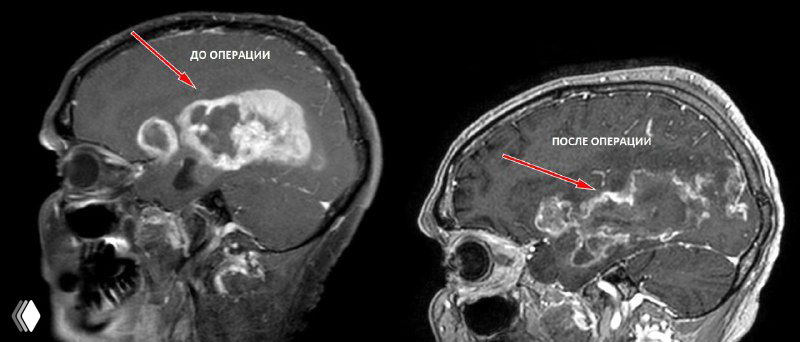

На снимках - глиобластома заполняющая больше половины правого полушария головного мозга.